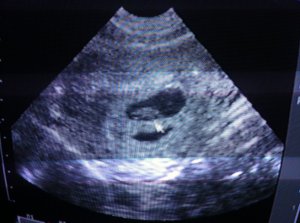

Felkerestem az ország egyik legjobb orvosát… Mit ad Isten –mert a Sorsban már akkor is rendületlenül hittem- szintén teljesen ismeretlenül soron kívül elvállalt, sőt különösen segítőkész volt az első pillanattól… Innentől beindultak az események, olyannyira, hogy csak kapkodtam a fejem… Vizsgálat itt, vizsgálat ott, persze minden rendben… A protokoll szerint ilyenkor 5 inszemináció következik… Az első sikertelen… Már akkor éreztem, hogy nem ez a mi utunk… Hogy ezzel nem fog sikerülni… Kértem az orvost, hogy „lépjünk tovább”, mert ezzel csak az időt vesztegetjük… Hihetetlen, de a professzor hitt nekem. Külön orvosi stáb ült össze, akik nem támogatták a lombikot a mi esetünkben, hiszen nagyon fiatalok és egészségesek vagyunk… De az orvosom hitt nekem, és kiállt mellettem… Így következtek az új procedúrák, új protokollokkal… Hogy naponta szurkálni kellett a saját hasamat, na arra már nem is emlékszem… Illetve arra igen, hogy hihetetlen örömmel döftem magamba a tűt mindennap, hiszen tudtam, hogy miért, illetve kiért teszem. És itt el is kezdődött, ami a mai napig tart, hogy egy Anya mindenre képes a gyermekéért… Jött a műtét (na az altatástól kicsit féltem, de utólag már az is homályba merült), rengeteg petesejt (talán 15), nagy boldogság, és indult a várakozás… Telefonok jöttek mentek, ahogy ez ilyenkor lenni szokott… Hurrá, minden a legjobb úton halad, még válogatni is lehet, annyi petesejt termékenyült meg… Akkor már éreztem, sőt tudtam, hogy eljött a mi időnk… Annyira összeállt a kép, hogy ennek így kellett lennie… Hogy ezzel a rengeteg kedves emberrel nekünk, ott és akkor meg kellett ismerkednünk… Hogy a házasságunkat semmi nem erősíthette volna meg jobban, mint ez a titok, amit ketten kellett, hogy cipeljünk… Hogy volt időnk várni arra, amit mindennél jobban szerettünk volna… És tudtam, hogy a Ő tökéletes lesz… Ott és akkor tudtam, hogy ezt az utat kellett végigjárni ahhoz, hogy egy tökéletes gyermek érkezhessen, egy végtelenül összetartó Papához és Mamához… Mi több, abban is biztos voltam, hogy kislány lesz, hiszen –elnézést kérek minden férfitől- mi nők mindenre képesek vagyunk, mindent kibírunk…

Folytatás az áldott állapottól, ami már semmiben nem tért el az átlagostól… Illetve talán mégis… Hiszen az sem volt problémáktól mentes, de a végére a lehető legjobban alakult…